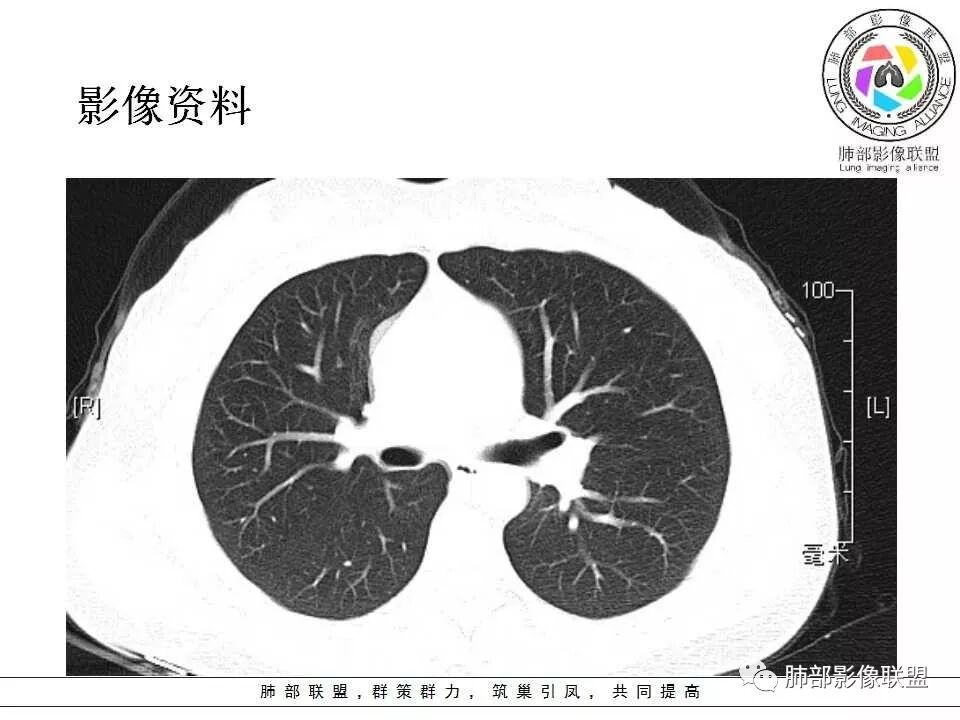

学习一下南大的诊断思路,左肺门区病灶,应该没跨叶,感觉都在上叶,强化密度均匀,边缘清晰,与支气管关系不大,常规考虑良性病变,PSP可能性大,鉴别CD,血管源性。但是一年增大怎么解释,不知道增大多少。

左肺病灶与支气管关系密切,类癌粘膜下生长,支气管略变窄,支气管外病变较大,符合冰山征表现,一年内有增长,考虑类癌,鉴别PSP,建议薄层重建。

我怎么又感觉跨叶间裂了,而且有胸膜尾征和可疑的指状突起,强化很明显,考虑SFT可能大,鉴别类癌和CD

左肺上叶后段紧贴斜裂结节影,支气管通畅,斜裂无移位,说明病灶来源斜裂可能,强化密度均匀,边缘清晰,考虑良性病变,PSP可能性大,鉴别CD。

青年女性,左肺门占位。定位:跨叶间裂,下叶邻近支气管推压,考虑肺外病变。影像表现:血管贴边,边缘光滑,强化均匀,考虑良性病变,PSP可能大,鉴别CD。

青年女性,一年前发现肺结节,复查有增大,未见近期片对比,定位:左肺上叶左肺门旁见实性类圆形结节,边界清晰光整,有部分分叶征,增强有均匀强化,与左上叶后段支气管关系不好判断,左上叶后段支气管未显示,堵塞?狭窄?需冠矢状面看看,定性:常规考虑良性或低度恶性肿瘤,典型的类癌或硬化性肺细胞瘤psp可能,神经源性或神经内分泌肿瘤、巨淋巴结增生症CD不除外,转移瘤、孤立性纤维瘤待排,建议HRCT或支气管镜检查。

年轻女性,左肺门区占位,斜裂推移未跨叶,类圆形,增强扫描明显强化,和支气管关系显示不是太清楚,感觉关系不是太密切,未见阻塞性炎症,一年后有长大,首先考虑PSP,鉴别类癌,SFT。